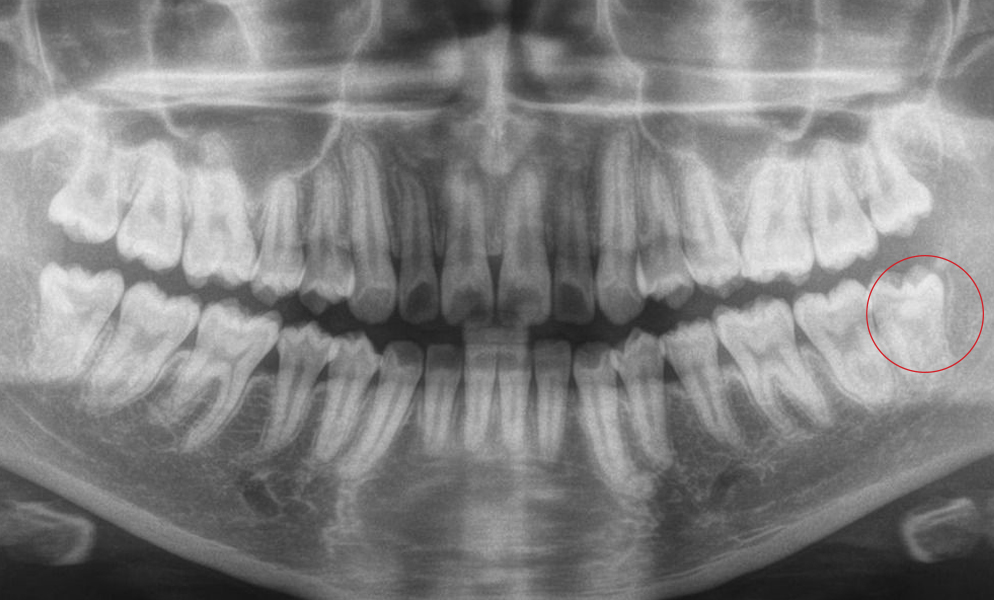

| Before | After |

![]() |

| Extraction of the third molar followed by autologous dentine graft | |